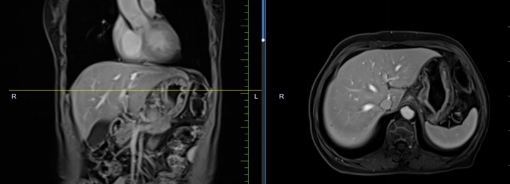

患者馬某某,男,60歲,因腹部不適行胃鏡及腹部CT,提示胃癌、多發(fā)淋巴結轉(zhuǎn)移、肝轉(zhuǎn)移,胃部病灶大小約11*6cm,淋巴結最大病灶約6*3cm,肝臟病灶最大約8.8*7cm。經(jīng)6周期化療+免疫,聯(lián)合中醫(yī)中藥后,病灶明顯縮小,進入維持治療階段,身體狀況與常人無異。

治療后